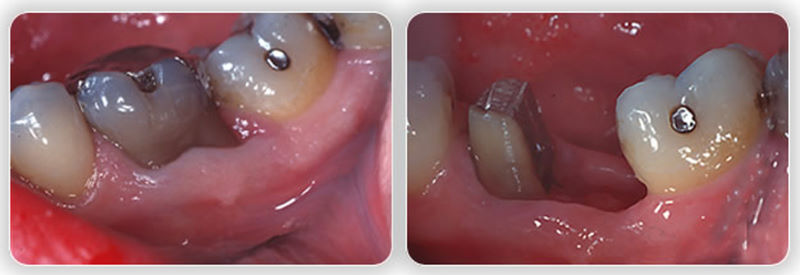

Гемисекция: фото до и после